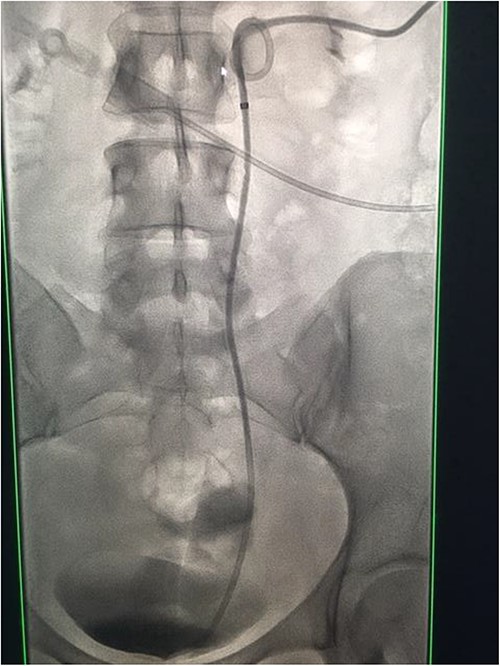

Under conscious sedation, using the previously inserted right percutaneous nephrostomy, antegrade access was achieved into the intrarenal collecting system and then into the proximal ureter. An 8 Fr × 11-cm access sheath was introduced. A guidewire was advanced antegradely through the site of ureteric transection and coiled in a position adjacent to the position of the guidewire that had been inserted retrogradely. A Gooseneck snare catheter was then passed over the guidewire and the snare was inserted (Figs 4 and 5). Under fluoroscopic guidance, the retrograde wire was retrieved and brought externally via the nephrostomy site, achieving through-and-through wire access (Figs 6 and 7).

Fluoroscopic images showing the antegrade Amplatz gooseneck snare catheter attempting to grasp the retrograde wire.